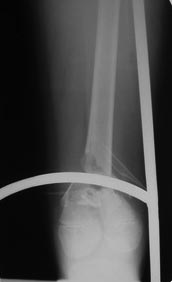

Переломы оскольчатые обеих бёдер в н/3, открытые. Раны ушиты в отличном состоянии.

На одном бедре межмыщелковый перелом и там мыщелки немного разъехались. Голень там тоже сломана в н/3 обе кости. Снимок голени в боковой проекции сделан не был.